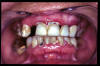

CM Edentulismo parcial, restos radiculares, caries y placa bacteriana